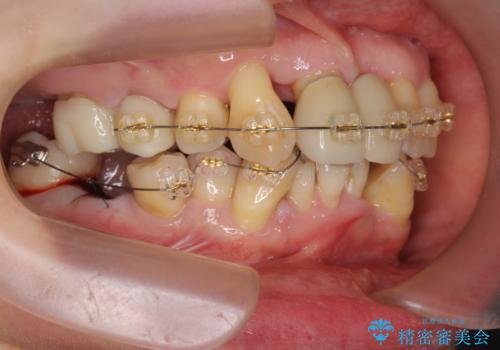

このままの歯並びでは仮にインプラントを埋入したとしても歯ブラシがしづらく、また歯周病の問題が再発しやすい、と判断し矯正治療を行ったのちに歯周病治療、インプラント治療を行っていく治療計画としました。

インプラント治療に加え、歯周病に対しての再生治療や歯周ポケットの除去を行う歯周外科、矯正治療、と必要な治療は多岐に渡りましたが、最終的に安定した噛み合わせを得られたとともに、清掃のしやすい口腔内環境を確立できました。